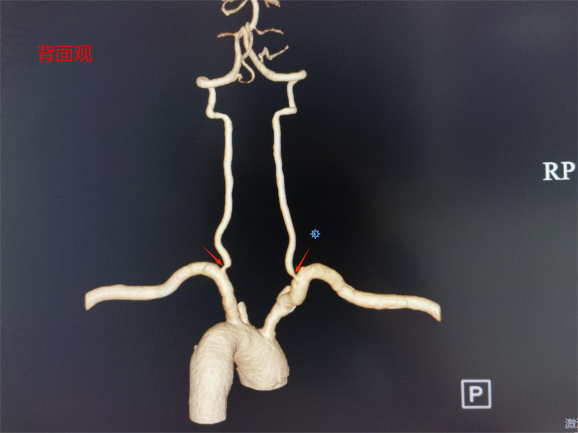

家住桂林的王大叔近半年来反复出现头晕、头疼,并伴有感觉脚踩棉花、行走不稳的症状,这些症状给他带来了极大的困扰,严重影响了他的日常生活。在家人陪伴下王大叔来到中南大学湘雅二医院桂林医院就诊,经过专业医疗检查,医生发现其双侧椎动脉起始段存在重度狭窄。椎动脉是向脑部供血的重要血管之一,如果它严重狭窄就会导致大脑的血液供应减少(后循环缺血),从而引发上述症状。

桂林医院血管外科舒畅教授团队经过仔细评估,决定采用微创腔内治疗,植入椎动脉支架进行治疗。右侧椎动脉微创血管重建手术具有创伤小、恢复快、效果显著等优点,是治疗血管狭窄的常用手段之一。